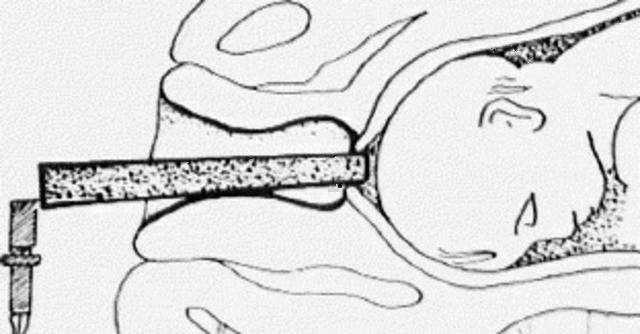

• Amnioscopía

Amnioscopía

"Técnica de exploración clínica de la gestante, que puede realizarse a partir de las 37 semanas de amenorrea". (EcuRed)